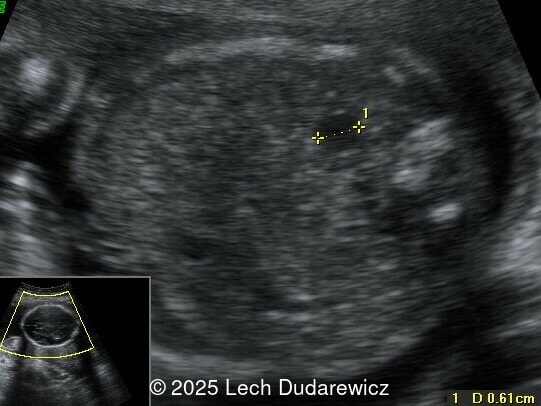

Structural anomalies were observed in multiple organ systems. The fetal skeleton showed hypoplastic iliac bones, rib deformities, hypoplastic scapulae, and excessive cervical spine lordosis. The fetal hands exhibited abnormal alignment of the fingers with restricted movement, and both feet were clubbed. Subcutaneous edema was noted over the forehead and occiput with a small cystic hygroma, along with increased nuchal fold thickness at 5.6mm, indicative of soft tissue edema. Additional abnormalities included mild pyelectasis. The fetal stomach appeared nearly empty, likely reflecting impaired swallowing or associated anomalies. Polyhydramnios was also noted. External male genitalia appeared normal. Cardiac evaluation revealed multiple echogenic foci within the left ventricle and an atrioventricular septal defect. While the heart's overall structure and function were otherwise normal, these findings added to the overall suspicion of a syndromic condition.

Other findings on prenatal ultrasound include soft tissue edema, facial anomalies, cardiac defects, and renal abnormalities. Soft tissue findings, including increased nuchal fold thickness and generalized subcutaneous edema, are common in campomelic dysplasia. Macroglossia and facial dysmorphisms, such as a flat nasal bridge or hypertelorism, may be observed but can be subtle on prenatal imaging. Polyhydramnios, frequently noted in affected pregnancies, may result from impaired fetal swallowing due to craniofacial or neurologic abnormalities. Cardiac anomalies, while not pathognomonic, include ventricular septal defects and echogenic intracardiac foci. Renal abnormalities, such as pyelectasis or enlarged kidneys, may also be present. These findings, although non-specific, contribute to the syndromic picture of campomelic dysplasia.